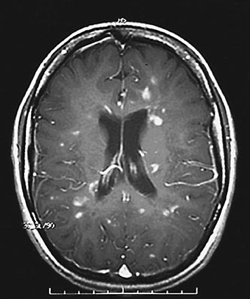

Asymmetric, periventricular lesions on MRI (Dawson's fingers)